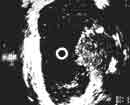

Эндовезикальное сканирование позволяет дифференцировать все слои мочевого пузыря (Рис. 1). Между мышечной стенкой и слизистой оболочкой визуализируется гипоэхогенная подслизистая соединительная ткань. При стадии рака мочевого пузыря Та (инвазия в пределах слизистой) создается впечатление, что опухоль отделена от мышечной стенки мочевого пузыря, то есть подслизистый слой остается неизмененным (Рис. 2), также хорошо визуализируются устья мочеточников. При распространении инвазии субэпителиальной соединительной ткани (стадия Т1) опухоль уже непосредственно прилежит к мышечному слою, но не инвазирует последний (Рис. 3).

Рис. 2. Цистэндосонограмма. Рак мочевого пузыря стадия Та.

1 - опухоль,

2 - устья мочеточников.